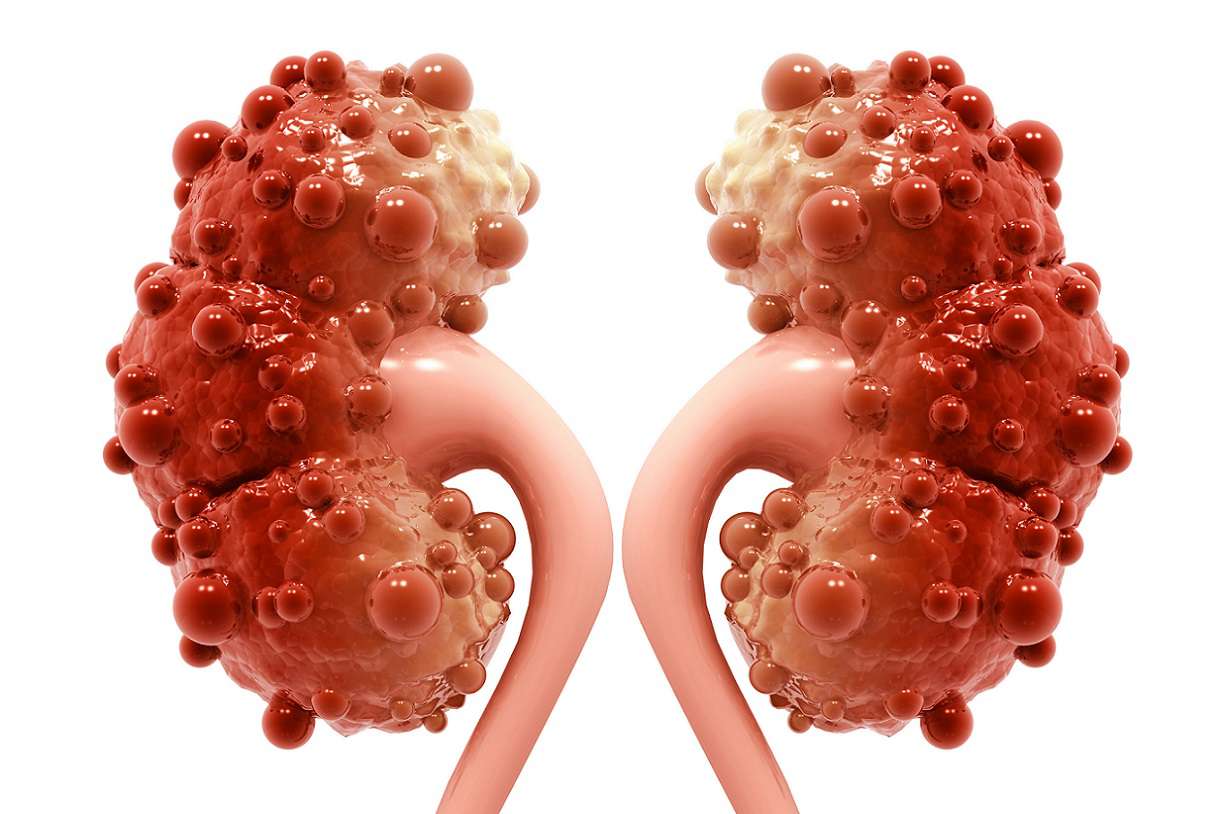

کیستهای کلیه کیسههای گرد و کوچکی هستند که بیشتر اوقات علائم و نشانه بالینی ندارند. کیستهای کلیه در دو گروه کیستهای ساده و بیماری پلیکیستیک قرار دارند. اکثر افراد مبتلا به کیست کلیه ساده از وجود کیست در کلیههای خودآگاه نیستند. معمولاً وجود کیست زمانی آشکار میشود که به دلیل مشکلات دیگری سونوگرافی یا آزمایشات تصویربرداری انجام میشود و یا کیست پاره شود و یا بهاندازهای بزرگ باشد که اندامهای اطراف را تحت فشار قرار دهد

کیستهای کلیه بهصورت کیسههای کوچک و دیواره نازکی هستند که با مایع پر شدهاند. با افزایش سن و یا به علت بیماری، کیستها ممکن است در سطح کلیه یا در جداره نفرونها ایجاد شوند. اندازه آنها میتواند از یک نخود تا یک گریپفروت متغیر باشد. بعضی از این کیستها در طول زمان به رشد خود ادامه میدهند اما بعضی دیگر اندازه ثابتی دارند.

دو نوع کیست کلیه وجود دارد که شامل کیستهای ساده و کیستهایی که در بیماری پلیکیستیک بروز میکنند. کیستهای ساده اغلب بر روی کلیهها و گاهی در لولههای نفرون ایجاد میشوند، دیواره نازکی دارند و حاوی مایعی آبکی هستند. این نوع کیستهای به کلیهها آسیب نمیزنند و بر عملکرد آنها تأثیر منفی نمیگذارند. اما در مقابل، بیماری کلیه پلی کیستیک (PKD) یک بیماری ارثی است که باعث ایجاد کیستهای متعدد بر روی کلیه یا درون نفرونها میشود. کیستهای PKD پتانسیل آسیب زدن به کلیه را دارند و حذف آنها مستلزم انجام اقدامات درمانی و مراقبتی است.